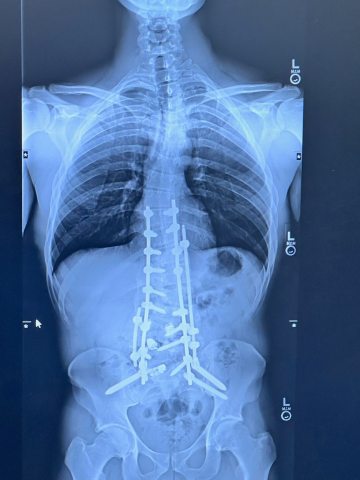

Xray after a scoliosis surgery

Randall's x-ray after surgery

Access to the newest technology, operated by best in class caregivers is vital to extraordinary level of care close to home, and it was lifechanging for Randall.

"I was born with a severe case of scoliosis and over the past 10 years it got progressively worse. My surgeries at 16 and 18 were steps toward relief, but the road was tough. The pain worsened, and finding a surgeon in my adult years to address my complex case seemed impossible.

Then came Dr. Ozpinar at Sacred Heart Medical Center. His honest approach and understanding eased my family's worries. In February 2023, he performed a transformative 11- hour surgery, freeing me from daily agony. Without Dr. Ozpinar, I'd have journeyed far for care, possibly to the East Coast.

I'm thankful for the partnership between a skilled surgeon and a caring community. This experience has taught me that challenges can be overcome with the right people by your side. He gave me my life back!"

-Randall, Eugene Spine Patient